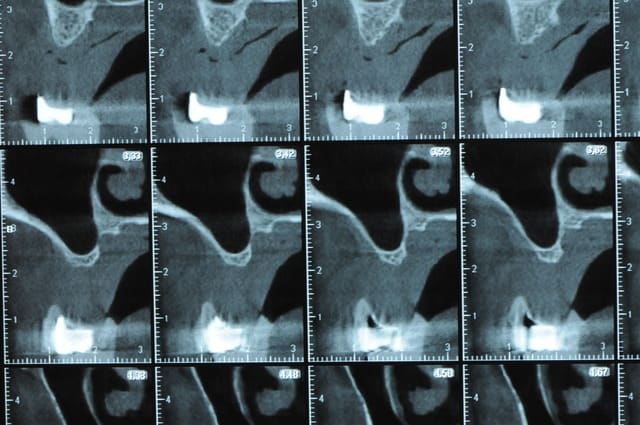

j'ai besoin de 4 implants au maxillaire pour faire tenir son complet.

dans la zone postérieur, pas de problème, mais devant, c'est une autre histoire.

Non sans décorner, superbe cas de début pour expansion, bone splitting et tout et tout.

la corticale a l'air tiptop, par contre en cas d'expansion il faut eventuellemnt augmenter le nombre d'implant à 6 pour compenser eventuellement le manque d'epaisseur 'avis personnel)

Je suis sceptique sur la gestion de ce cas par bone splitting puisqu'il met parait très difficile d'obtenir un volume osseux peri-implantaire crestal suffisant et satisfaisant.

+1 Olive, ce serait à mon avis plus prédictible avec des greffes. Je doute qu'on puisse obtenir suffisamment d'os en vestibulaire et en palatin des implants en splittant une crête aussi fine.